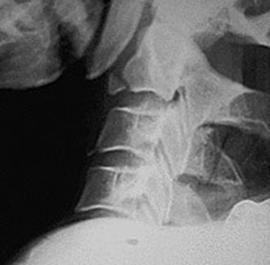

Fractura spanzuratului Fractura anterioara C4 Fractura C5 in lacrima in flexie

"in lacrima"

![]()

Fractura C5 "in lacrima" in extensie Luxatie fatetara

unilaterala Luxatie

fatetara bilaterala

C5 - C6 C5 - C6

Incidenta laterala Fractura Clay-Shoveler Luxatie atlanto-occipitala si